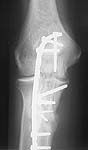

The attached case was similar, but not quite as comminuted.

3 months post-op: